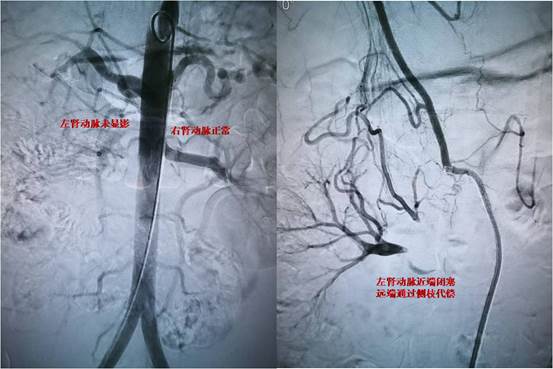

图-1 闭塞的肾动脉

患者,未成年男性,在当地因高血压病就诊检查,发现可能存在肾动脉狭窄可能,患者血压最高达200/146mmHg,为进一步诊治慕名来到交大一附院血管外科杨林教授门诊。患者入院后,在科室禄韶英主任指导下,杨林教授及诊疗团队韩阳医师,武士琪医师,李小兵医师对其进行了完善的术前检查、术前准备及药物治疗。进一步明确患者为肾动脉闭塞,手术难度极大,手术风险极高。考虑到患者未成年,为保留患者潜在的肾功能,同时避免采用常规的金属支架技术。杨林教授团队经过详细的术前讨论后和设计手术方案后,决定给患者实施局麻微创的药物球囊成型技术。在介入手术室的配合下,发现患者为右肾动脉闭塞,远端通过毛细血管代偿,手术团队通过精细的微创技术,反复尝试都未能通过闭塞段血管,最后通过各种微导丝、微导管技术的联合应用终于通过闭塞的肾动脉,然后通过小球囊预扩张,过渡到常规球囊扩张,最后为患者实施药物球囊扩张成形术,患者闭塞的肾动脉得到完美重建。患者术后在血管外科医护团队的严密监控下顺利恢复。术后血压即恢复正常,于近日顺利出院。